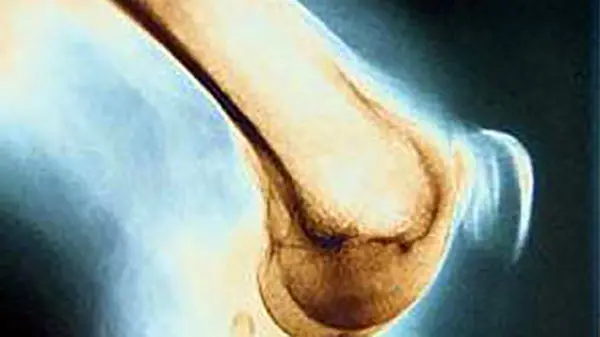

مفاصل نقش بسیار مهمی در فعالیت روزمره دارد. حفظ سلامت مفاصل‌ از اهمیت ویژه ای برخوردار است. مفاصل را باید با ورزش و تحرک داشتن سالم نگه داشت. آرتریت که التهاب مفاصل است در بسیاری از افراد شایع است. در ادامه راهکارهایی برای حفاظت از مفاصل ارائه شده است.

به گزارش رکنا، افراد مبتلا به آرتریت (التهاب مفاصل) می‌توانند با اعمال راهکارهایی، درد خود را کاهش داده و با افزایش امکان حرکت، توان انتقال و جابه جایی خود را بهبود بخشند.